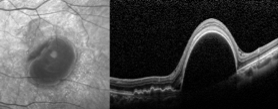

老王左眼檢查圖片